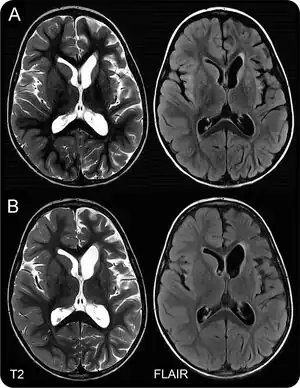

In suspected cases, physicians perform diagnostic testing using a protein-detecting test that identify anti-Hu antibodies, if present. Another test involves examining the fluid that bathes the brain and spine, although this test is less specific for the disease. Physicians may also use a special imaging device, known as magnetic resonance imaging (MRI), which can take pictures of the patient's brain and detect signs of inflammation that suggest ongoing disease. An electroencephalogram (EEG) is another tool that can be done to clarify whether anti-Hu encephalitis is the underlying cause of a patient's symptoms. This is a test that involves placing probes on a person's head to detect electrical brain activity. Certain patterns of activity can be indicative of brain disease. In the case of anti-Hu encephalitis, temporal lobe electrical activity changes and the length of certain electrical waves known as delta and theta waves become slowed.[1]